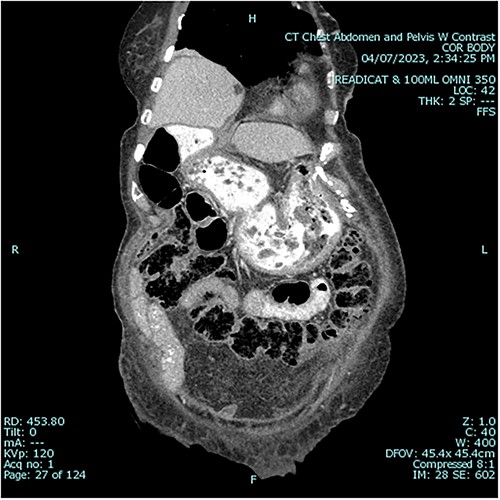

A 79 year old female patient presented to the emergency department with a two-day history of intractable nausea, vomiting, and diffuse abdominal pain. She reported having had a left groin bulge for 70 years and did not regularly see a doctor. Vital signs were notable for tachycardia and tachypnea. Physical exam was notable for a firm and distended diffusely-tender abdomen; and an associated giant incarcerated left inguinal hernia, extending down to the thigh. Laboratory evaluation revealed leukocytosis (WBC 20 K/uL), lactic acidosis (lactate 5 mmol/L), and acute kidney injury (Cr 1.5 mg/d). Computed tomography imaging demonstrated a giant left inguinal hernia containing the stomach, proximal duodenum, right hemicolon, and omentum, and associated free intraabdominal fluid and pneumoperitoneum (Fig 1). Aggressive intravenous fluid resuscitation, broad spectrum antibiotics, and vasopressor-support were started for septic shock secondary to perforated viscus. The patient was taken emergently to the OR for exploratory laparotomy. Operative findings included the following: left inguinal hernia containing the aforementioned structures, herniation of the stomach with severe gastric distension, a 0.5 cm diameter gastric perforation with surrounding necrosis at the mid portion of the lesser curve, and large volume ascites containing gastric contents. Operative interventions included the following: manual reduction of bowel and omentum from the left inguinal hernia sac, wedge resection of the perforated stomach (Figs 2 and 3), and abdominal washout. The patient was noted to have loss of abdominal domain due to the longstanding hernia. Her abdomen was closed using a biological mesh in a bridging fashion, as the fascia could not be closed primarily. Wide drainage was achieved using four 19Fr Blake drains. After surgery, the patient recovered from septic shock while being cared for in the intensive care unit. Her postoperative course was complicated by atrial fibrillation, pulmonary embolism, and COVID-19 infection. Discharge to a rehabilitation center occurred on hospital day 20. Follow up computed tomography imaging is as shown (Fig 4). Staged repair of the left inguinal hernia with permanent prosthetic mesh is planned in the near future.

A Preoperative axial view at level of mid abdomen, demonstrating free intraabdominal fluid and air 1b: Preoperative axial view at level of groin, demonstrating stomach-containing left inguinal hernia 1c: Preoperative axial view at level of the mid thigh, demonstrating left inguinal hernia containing both the stomach and other viscera 1d: Preoperative coronal view, demonstrating stomach being pulled down into inguinal hernia sac 1e: Preoperative sagittal view, demonstrating stomach being pulled down into inguinal hernia sac, and associated free intraabdominal air.